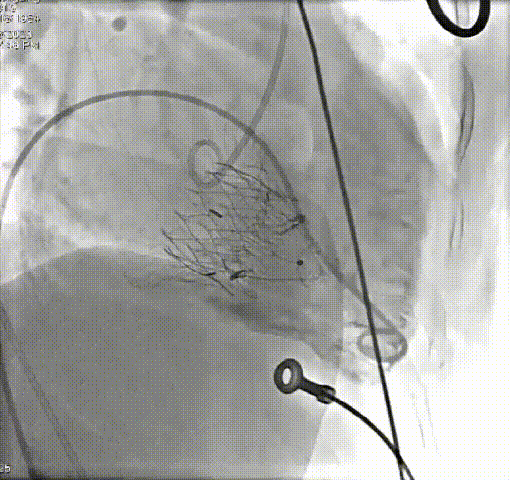

术前、术后造影结果

患者79岁,女性,“心房颤动”病史5年,近5个月出现活动时气促、双下肢水肿、乏力。“高血压”病史10年。心脏超声:极重度三尖瓣关闭不全,轻-中度二尖瓣关闭不全。TTVR术后三尖瓣关闭不全消失,轻微瓣周漏。